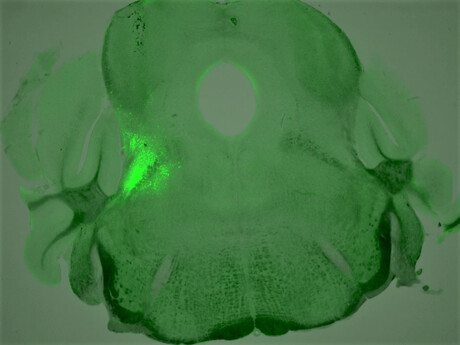

To develop strategies to rescue OIRD with more specificity, Assistant Professor Sung Han and his team at the Salk Institute for Biological Studies set out to search for the breathing neurons in the brain that also carry opioid receptors. The researchers identified a group of neurons that express a certain type of opioid receptor (the mu opioid receptor) and are located in the brainstem breathing modulation centre; they then characterised these neurons’ role in OIRD.

They found that mice that were genetically engineered to lack opioid receptors in these neurons didn’t have their breathing disrupted when exposed to morphine, as mice in the control group did. The researchers also found that, without introducing opioids, stimulating these receptors in control mice caused symptoms of OIRD.